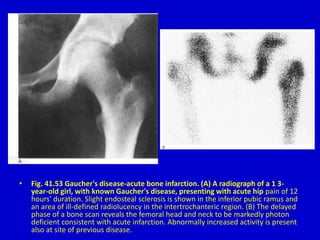

• Fig. 41.53 Gaucher's disease-acute bone infarction. (A) A radiograph of a 1 3-

year-old girl, with known Gaucher's disease, presenting with acute hip pain of 12

hours' duration. Slight endosteal sclerosis is shown in the inferior pubic ramus and

an area of ill-defined radiolucency in the intertrochanteric region. (B) The delayed

phase of a bone scan reveals the femoral head and neck to be markedly photon

deficient consistent with acute infarction. Abnormally increased activity is present

also at site of previous disease.

• Fig. 41.53Gaucher's disease-acute bone infarction. (A) A radiograph of a 1 3- year-old girl, with known Gaucher's disease, presenting with acute hip pain of 12 hours' duration. Slight endosteal sclerosis is shown in the inferior pubic ramus and an area of ill-defined radiolucency in the intertrochanteric region. (B) The delayed phase of a bone scan reveals the femoral head and neck to be markedly photon deficient consistent with acute infarction. Abnormally increased activity is present also at site of previous disease.